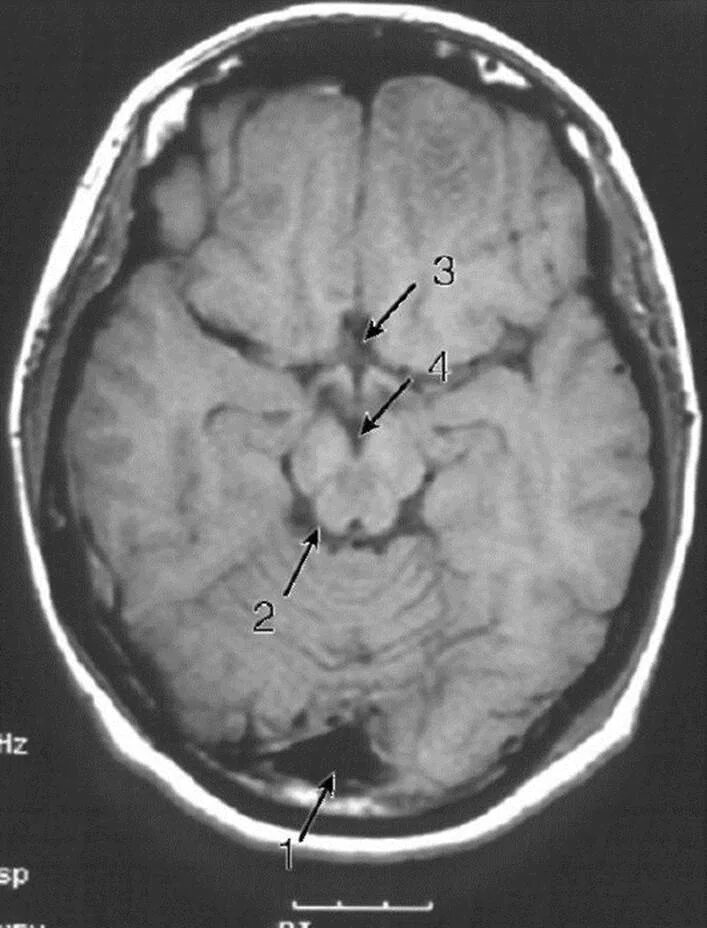

Цистерны на кт